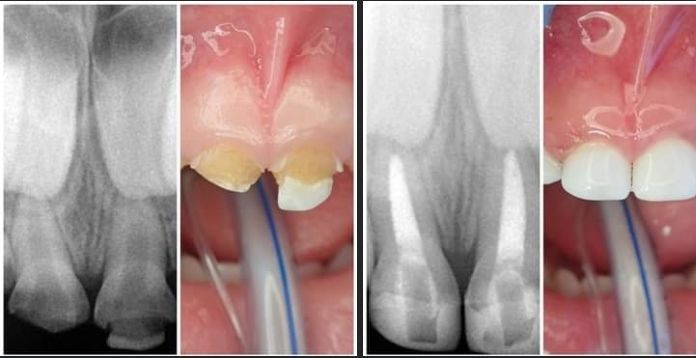

TRATAMIENTO DE CARIES DENTAL

- Eliminación de caries en etapas tempranas con técnicas de mínima invasión.

- Tratamientos efectivos para cavidades avanzadas, protegiendo los dientes temporales y permanentes.